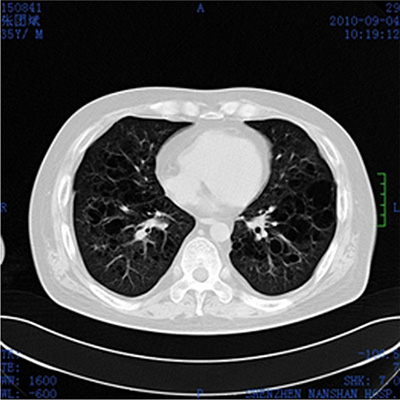

Laboratory examination revealed that the patient’s erythrocyte sedimentation rate (ESR) was 23 mm/1 h (≤ 15 mm/1 h) and CRP was 50 mg/L. Bone Marrow Examination revealed that the bone marrow nucleated cells containing 47% granulocytes composed of vacuoles and toxic particles and 41% erythrocytes composed of polychromatic erythroblast had obviously proliferated with an expanding pale area. TSH was 0.021 Miu/L (0.35–4.94), testosterone was 0.67 ng/ML, PRL was 57.60 ng/ML and cortisol was 12.70 ug/dl. Liver function showed that ALT was 194 U/L (≤ 40 U/L), AST was 135U/L (≤ 50 U/L) and LDH was 409 U/L (100–300 U/L). Lymphocyte subpopulation were composed of 26.30% NK cells, 9.57% CIK cells (a little higher), and 1.89% B cells (a little lower), which indicated a low-level humoral immunity. Pituitary MRI scan revealed that most of pituitary fossa showed a cerebrospinal fluid signal. The pituitary volume was significantly narrowed and was located at the sellar floor with a line sample. The infundibulum signal was thickened unequally with a change of empty sella. ECT bone scan showed irregular radioactive concentration shadow of the sternum, bilateral ilium and hip joint, which indicated an active metabolism of bone mineral. Bonchoalveolar lavage luid routine showed that total nucleated cells were 280 × 106/L in which monocyte occupied 85% and coenocyte occupied 15%. The lavage fluid bacterial culture indicated the infection of viridans streptococcus. CD4/CD8 was declined (0.95%). The result of CD1α macrophage reaction was positive (+). CT plain scan showed a T2 high signal nodular shadow with a length of 8mm in the right eye orbital wall. Brest CT showed that there were higher penetrance of lung fields, extensive unequal-sized flake or cystic bright shade, and incrassate shade of interlobular septum (Figure 2). Abdomen B ultrasonography revealed that his liver was enlarged. The scalp lesion pathology showed dermal papilla edema and abundant hyperplastic large round cells, in which we could see nuclear groove, several eosinophile granulocytes and infiltrated lymphocytes (Figure 3A and 3B). Immunohistochemical examination (Figure 4A and 4B) showed that histioid cell cytoplasm and nucleus were CD1a (+) and histioid cell cytoplasm were CD68 (+). Pathology of the alar skin ulcers showed that there were diffuse patchy medium sized hyperplastic cells. The actively proliferating cells have folding and sagging nucleus, smooth and exquisite chromatin and thin nuclear membrane. The common expression pattern of these cells was S-100 (+), CD1a (+), CD68 (+), CD3 (−) and CD79a (−). About 20% cells express the cell proliferation marker Ki-67.

Figure 2: Brest CT plain scan. Higher penetrance of lung fields, extensive unequal-sized flake or cystic bright shade, and incrassate shade of interlobular septum.